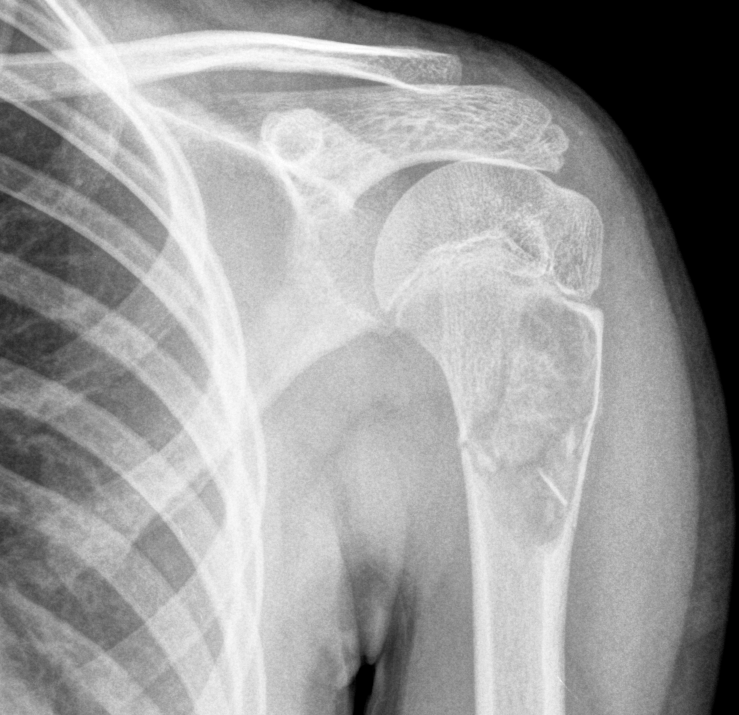

3. Unicameral cyst fallen fragment sign